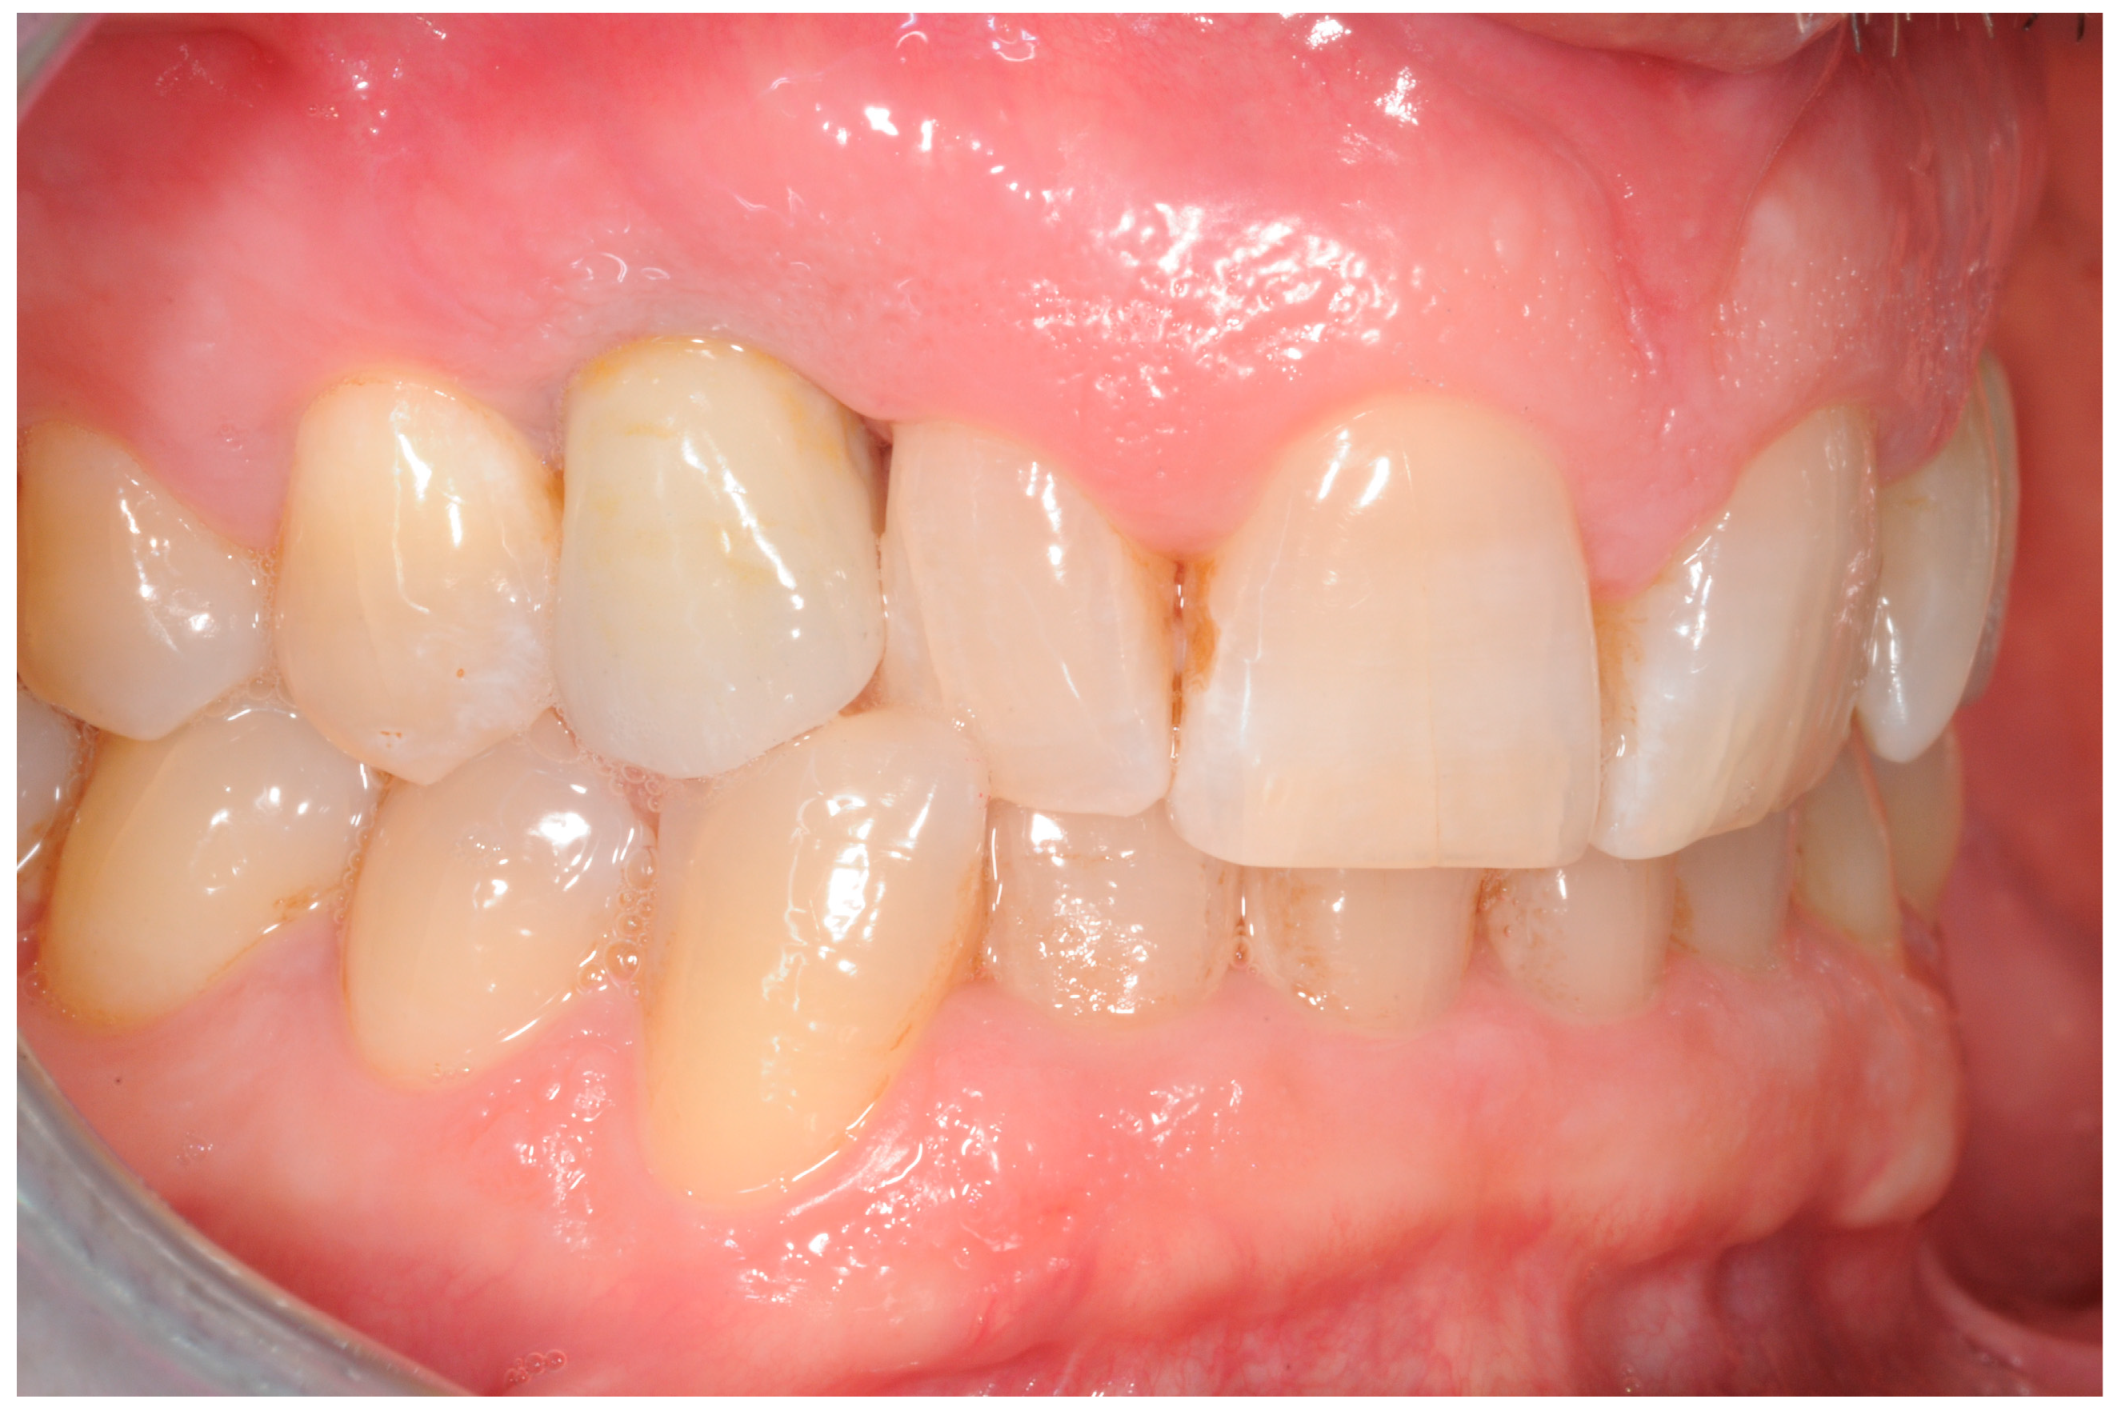

- Group 1: An implant-level impression adopting an open-tray impression technique was adopted using a polyvinylsiloxane impression material. After pouring the cast, an angled abutment was chosen, and a partially-veneered zirconia crown (limiting the veneering process to the vestibular surface) was obtained. At a second appointment, the abutment was screwed to the implant, and the crown was checked following the CMO (contact, margins, occlusion) acronym. The abutment was then manually screwed to the implant and secured at 25 Ncm. The access hole was closed with Teflon tape, and the crown was cemented with glass ionomer cement. (FujiCem 1, GC Europe, Leuven, Belgium) (Figure 1 and Figure 2).